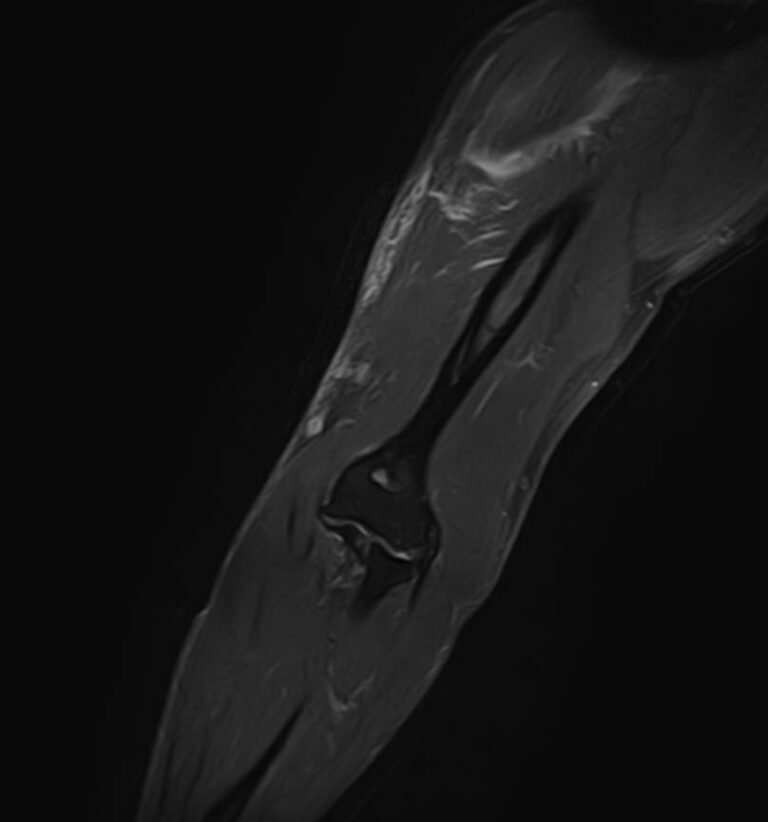

Магнитно-резонансная томография применяется для обследования мягких тканей верхних и нижних конечностей, включая кожу, подкожно-жировую клетчатку, мышцы, фасции, межфасциальные пространства, сухожилия, связки, сосудистую систему, лимфоузлы и лимфатические протоки, нервные волокна, надкостницу и костный мозг.

Кроме того, имеет значение показатель индукции магнитного поля томографа. Наша клиника оснащена современным высокопольным томографом последнего поколения TOSHIBA VANTAGE TITAN 1,5 Тесла. Высокая индукция магнитного поля обеспечивает повышенную четкость изображений при обследовании мягких тканей конечностей. За счет послойного сканирования в различных плоскостях с шагом от 1 мм и последующего преобразования данных в объемные изображения томограф обеспечивает выявление мельчайших изменений в тканях. Это позволяет проводить диагностику различных заболеваний на самых ранних стадиях.

- Травматические повреждения (растяжения, разрывы мышц, связок, сухожилий)